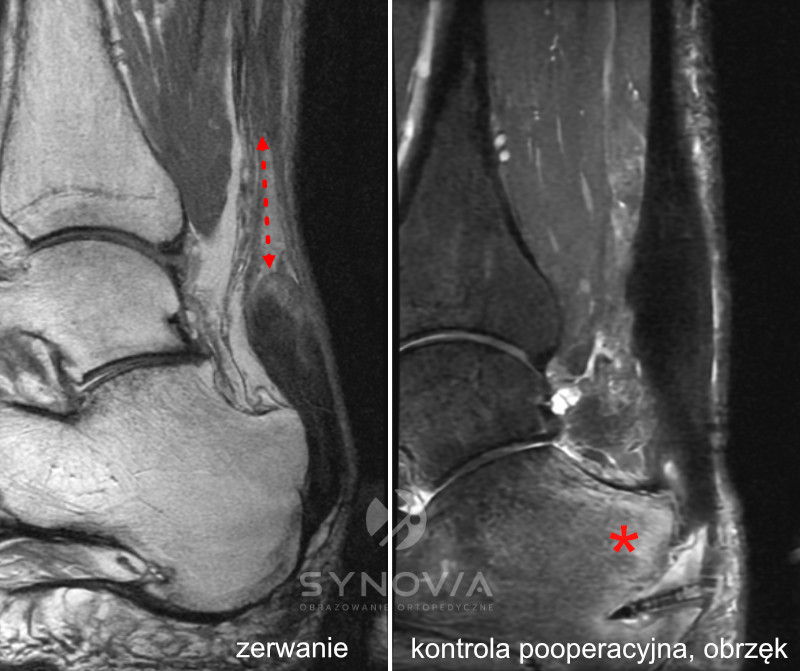

MRI

Co widać: Stopień uszkodzenia ścięgna, obrzęk w kości piętowej, stan tkanek okolicznych, możłiwy dokładny monitoring gojenia, w tym gojenia pooperacyjnego.

Rezonans magnetyczny (MRI) Wykonywany jest w przypadkach niejasnego obrazu klinicznego, braku poprawy mimo leczenia, podejrzenia zmian w obrębie kości lub struktur głębokich oraz przy planowaniu leczenia operacyjnego. MRI szczególnie dobrze obrazuje obrzęk szpiku kostnego i zmiany w tkankach miękkich.